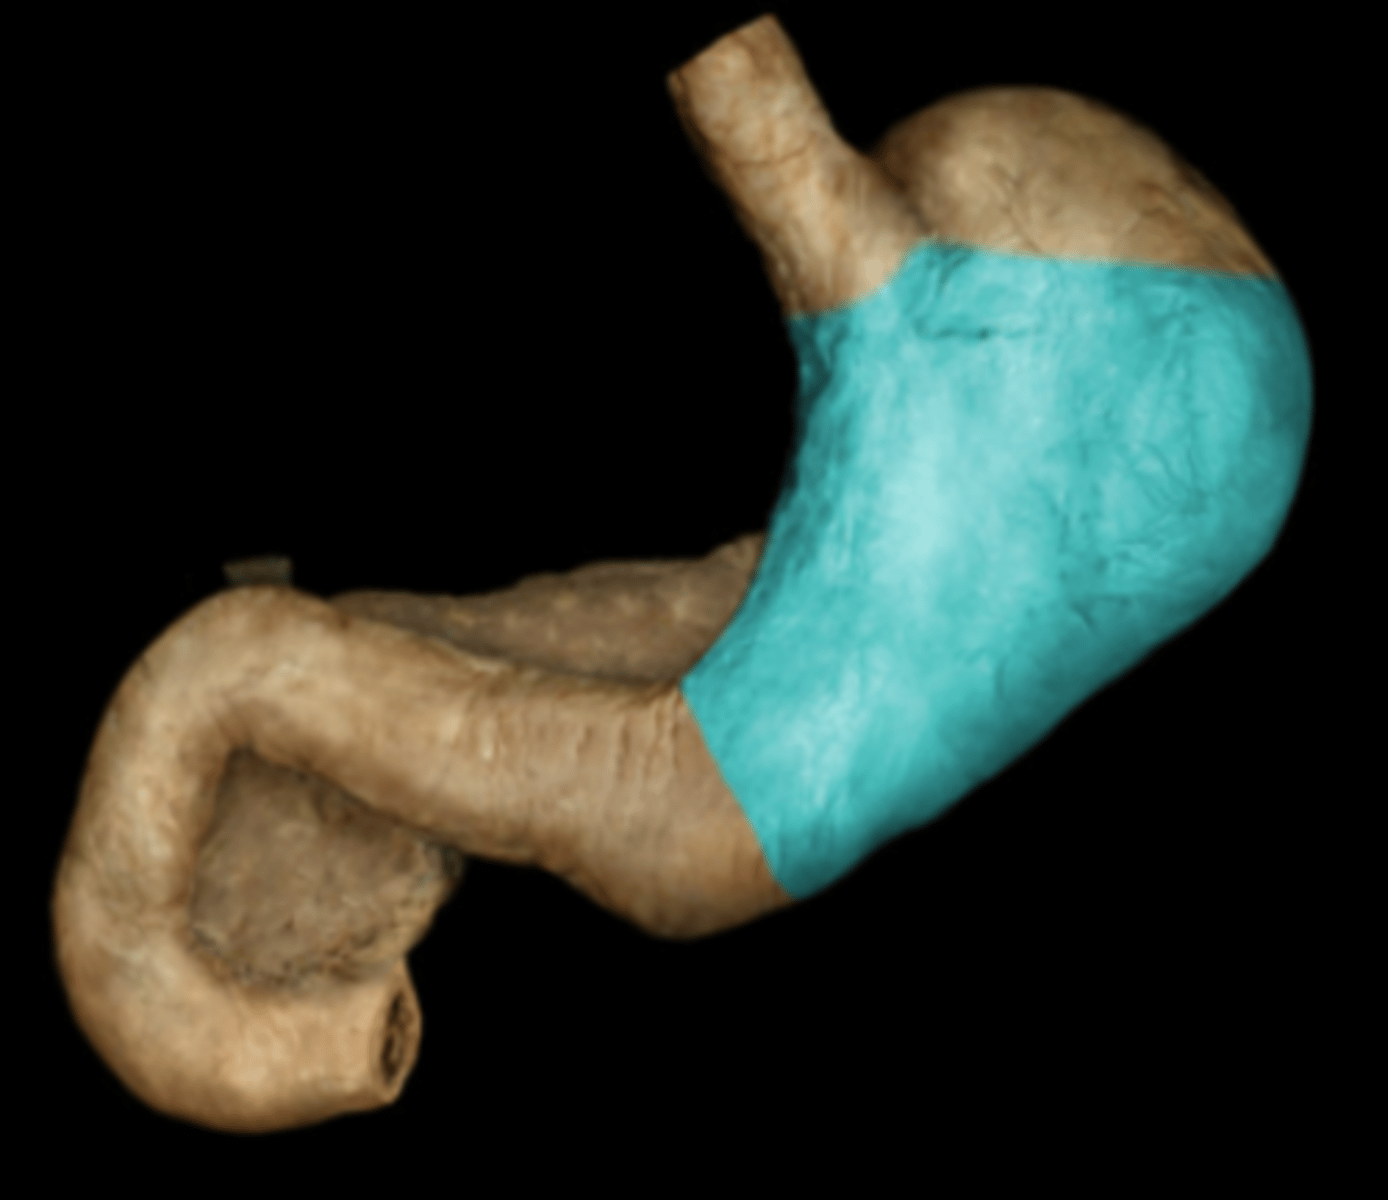

Cardia

Fundus

Body

Pylorus

Greater Curvature

Lesser Curvature

Duodenum